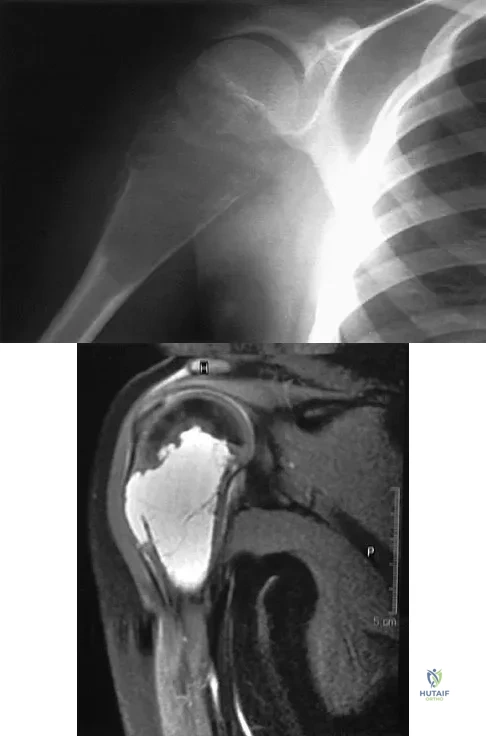

Question 8:

Figure 37 shows the radiograph of a 23-year-old football player who sustained a blow to the anterior aspect of his shoulder. Examination reveals pain and limited rotation. He is unable to flex the arm above the shoulder. Management should include which of the following studies?

Options:

- Axillary radiograph

- Arthrogram

- Electromyogram

- Bone scan

- Arteriogram

Correct Answer: Axillary radiograph

Explanation:

The patient has a posterior dislocation. The radiograph reveals marked internal rotation, but fails to show whether the humeral head is posteriorly displaced. Therefore, an axillary radiograph should be obtained to help confirm the diagnosis. Transverse view CT or MRI scans also may be useful. The other studies will not help confirm the diagnosis. In addition to a direct posterior blow, a shoulder dislocation may be caused by a seizure disorder or electrocution. Bloom MH, Obata WG: Diagnosis of posterior dislocation of the shoulder with the use of Velpeau axillary and angle-up roentgenographic views. J Bone Joint Surg Am 1967;49:943-949.

References:

Rockwood CA: Subluxations and dislocations about the shoulder, in Rockwood CA, Green DP (eds): Fractures in Adults, ed 2. Philadelphia, PA, JB Lippincott, 1984, vol 1, pp 806-856.